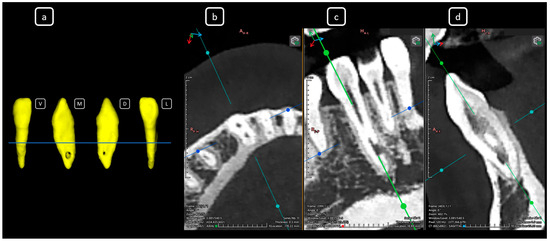

Cone beam computed tomography (CBCT) is a valuable diagnostic tool for evaluating the upper airway and maxillofacial region. This report demonstrates the clinical value of CBCT in identifying significant anatomical variations in endodontics, incidentally detected on a non-endodontic CBCT scan. A 23-year-old female patient underwent CBCT imaging at the Faculty of Dentistry-UJED to evaluate her upper airway. CBCT imaging revealed a unique, complex, and unusual anatomy of mandibular root canals, characterized by Vertucci’s type III root canals in the anterior sextant and co-occurrence of bilateral C-shaped mandibular second molars (type C2 according to Fan’s classification). No therapeutic interventions were initiated due to the patient’s asymptomatic status. CBCT imaging is a valuable tool for integrated diagnostic approaches, underscoring its role in thorough patient management. The integration of multidisciplinary interpretation of CBCT data can enhance diagnostic accuracy and optimize patient records and management, emphasizing the importance of collaborative efforts between radiologists, clinicians, and endodontists. Documenting and sharing such findings can increase awareness of rare anatomical variations, facilitating detection and contributing to medical knowledge. Full article

Figure 1